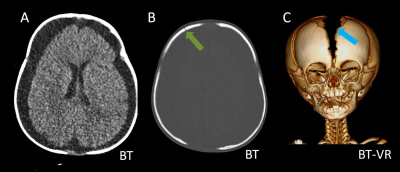

- A) Bilateral serebral konveksitede subdural higroma

- B) Kemik pencerede frontal kemikte sağda nondeplase kırık

- C) Süturlarda ayrışma

- İstismara bağlı kafa travmasında en sık saptanan radyolojik bulgular:

- Subdural hematom: En sık görülen radyolojik bulgudur, vakaların %83-90’ında saptanır. Genellikle bilateraldir ve farklı yaşlarda hemorajik elemanlar içerir.

- Subdural higroma: Araknoid yırtıklara bağlı gelişir. Köprü ven yaralanması ile birlikte olduğunda hemorajik bileşenler içerebilir (hematohigroma).

- Köprü ven trombozu: Manyetik duyarlılık görüntülemede, kortikal ven trasesinde duyarlılık artefaktı olarak ya da “lolipop” ve “iribaş” (tadpole) işareti şeklinde görülür. Vakaların yaklaşık %30-45’inde saptanır.

- Kalvaryal kırıklar: Tek başına istismar ilişkili kafa travması açısından spesifik olmasa da çoklu kırıklar istismara bağlı travma şüphesini artırır.